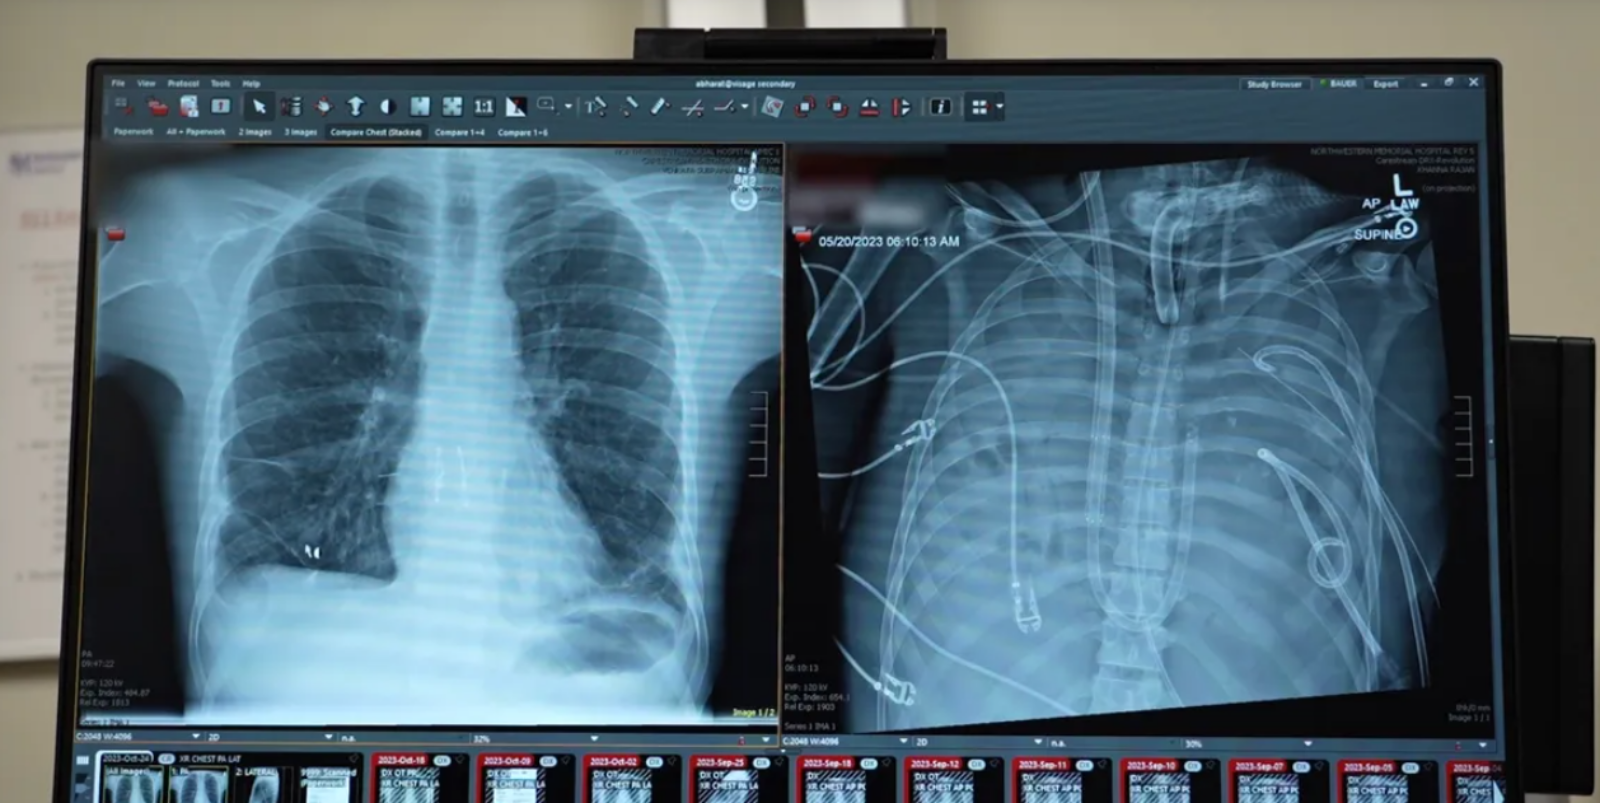

Ako informuje web IFL Science, dovtedy zdravý 33-ročný muž musel byť hospitalizovaný pre chrípku typu B. Trpel akútnymi respiračnými problémami, následne sa však do jeho tela dostala ešte baktéria Pseudomonas aeruginosa. Napokon sa u neho vyvinul nekrotizujúci zápal pľúc. Ani antibiotiká, ani kyslíková terapia nedokázali zvrátiť alebo aspoň zastaviť zhoršovanie jeho stavu, čo viedlo k zlyhávaniu srdca a obličiek.

Lekár sa podľa tlačovej správy uverejnenej prostredníctvom EurekAlert! k štúdii publikovanej v časopise Cell vyjadril, že pľúca pacienta sa takpovediac rozpúšťali a boli nenávratne poškodené. Bolo jasné, že bez transplantácie nemá šancu prežiť. Problémom ale bolo, že jeho organizmus bol v príliš zlom stave, aby zvládol taký náročný zákrok. Jediným spôsobom, ako dostať infekciu pod kontrolu, bolo pľúca odstrániť.

Lekári z Northwestern university z amerického Illinois tak čelili obrovskej výzve. Ako to urobiť tak, aby pacient prežil bez pľúc? Až donedávna to možné nebolo. Už v minulosti sa však podarilo zlepšiť stav pacientov trpiacich cystickou fibrózou tak, že ich telo niekoľko dní okysličovali umelé pľúca. Odborníkom sa podarilo vytvoriť stroj schopný napodobňovať funkciu pľúc. Zabezpečuje prísun kyslíka do krvi a odstraňovanie oxidu uhličitého, pričom udržiava prietok oslabeným srdcom.

Umelé pľúca, ktoré pomáhajú skutočným pľúcam pacienta, už boli vytvorené v minulosti, odborníci však teraz museli dať hlavy dokopy a prísť s inovatívnym riešením. Napokon sa to podarilo a len čo boli pľúca odstránené a pacient bol napojený na tie umelé, ostatné orgány sa začali uzdravovať.

O dva dni neskôr bol pacient pripravený na transplantáciu. Našťastie, tá sa vydarila. Lekári o prípade informovali až teraz, dva roky od riskantného kroku, aby si boli istí, že sa to naozaj podarilo a pacient sa mohol vrátiť do bežného života.